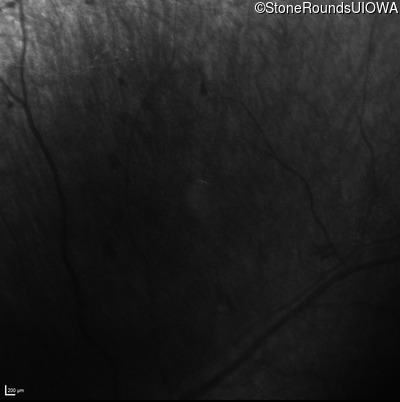

Infrared Fundus Photograph - Right - No Light Perception

Exemplar